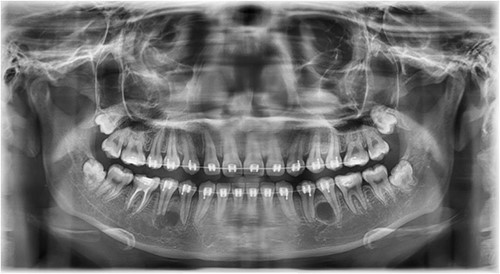

A Neumann full-thickness buccal flap was utilized to remove these during the course of orthodontic treatment. The shortcoming of the buccal surgical removal approach is that although it is better for visualization, it poses a high risk of trauma to the adjacent teeth or nerves [4, 5]. As the premolar was being removed on the right side, there was a fracture of the root apex (Fig. 2). On the left side, the premolar bud could be removed without any trauma to the adjacent tooth roots. After months of follow-up, there was normal bone formation, and no other symptoms were identified (Fig. 3).

Follow-up panoramic image 1-year after removal of the supernumerary premolars.

In this context, a buccal approach using a Neumann full-thickness flap was preferred (Fig. 4). When a buccal approach is planned, then the location of the mental nerve must be identified to avoid any post-operative sensory problems. The most challenging part is to exercise extreme caution during Ostectomy to avoid damage to the adjacent tooth roots.